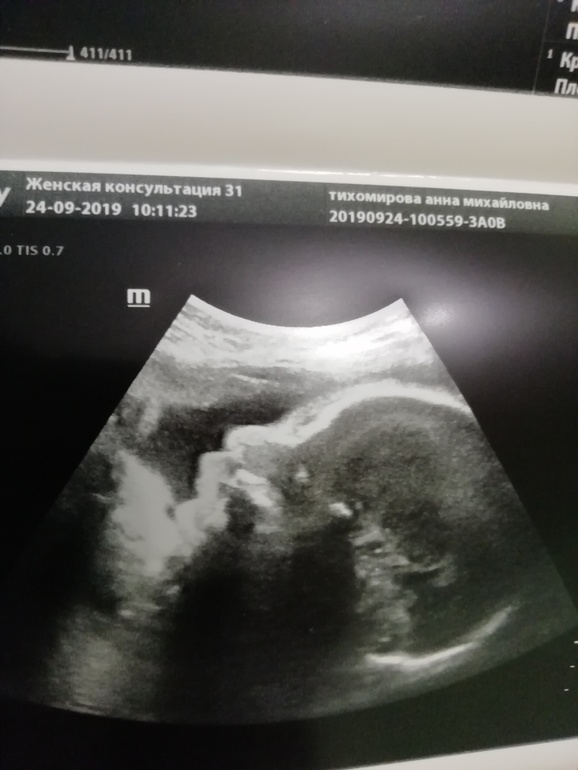

Сегодня 24.09 ходила на третий узи скриннинг.

Что имеем:

-по доплеру все отлично, кровотоки в норме

-малыш идет ровно в срок по замерам

-предполагаемый вес около 1500гр

-шейка закрыта и не укорочена

-⚠️плацента осталась в краевом предлежании, не поднялась ни на сколечко

- ❗вчера малыш лег в поперечное, как в гамаке, ему плацента видать внизу мешает встать головой нормально

Я, конечно, понимаю, что до 36 недель еще небольшой шанс на поднятие плаценты и его разворот есть, но уже и не надеюсь, потому что за всю Б плацента так и осталась в краевом предлежании.

Контрольное узи назначено на 33-34 недели.

А вот и малыш, не похож ни на брата, ни на сестру совсем 💙💙💙